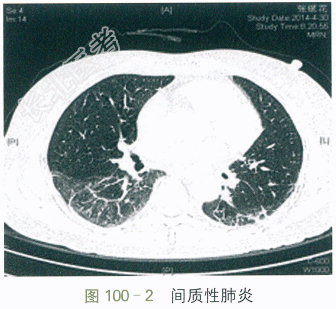

自身抗体:抗核抗体1:320,抗SSA抗体阳性,抗SSB抗体阳性,抗线粒体抗体阳性,抗ds-DNA抗体15.4IU/ml,抗核小体抗体2.0RU/ml。免疫球蛋白:IgG20.29g/L,IgA4.66g/L,IgM1.13g/L,IgE211.0IU/ml。血常规:RBC4.75×1012/L,Hb130g/L,WBC7.06×109/L,PLT298×109/L;ESR51mm/h;hs-CRP7.6mg/L。补体:C31.33g/L,C40.23g/L。血气分析:pH7.45,PaCO238.0mmHg,PaO265.0mmHg,SaO293.0%;乙肝免疫标志物、丙肝抗体、HIV抗体全阴性。肺HRCT:两肺间质性炎症(见图100-2)。腹部B超:肝脂肪浸润。心超:未见异常。肺功能:中度限制性通气功能障碍。